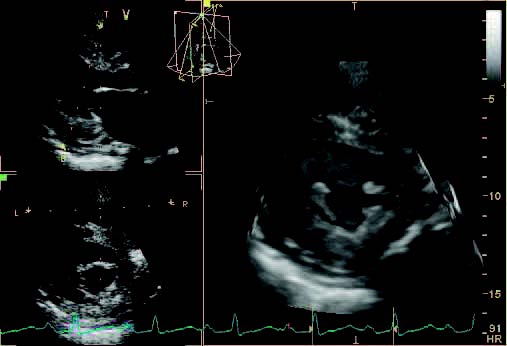

- B-Mode

- Dual screen

- Quad screen